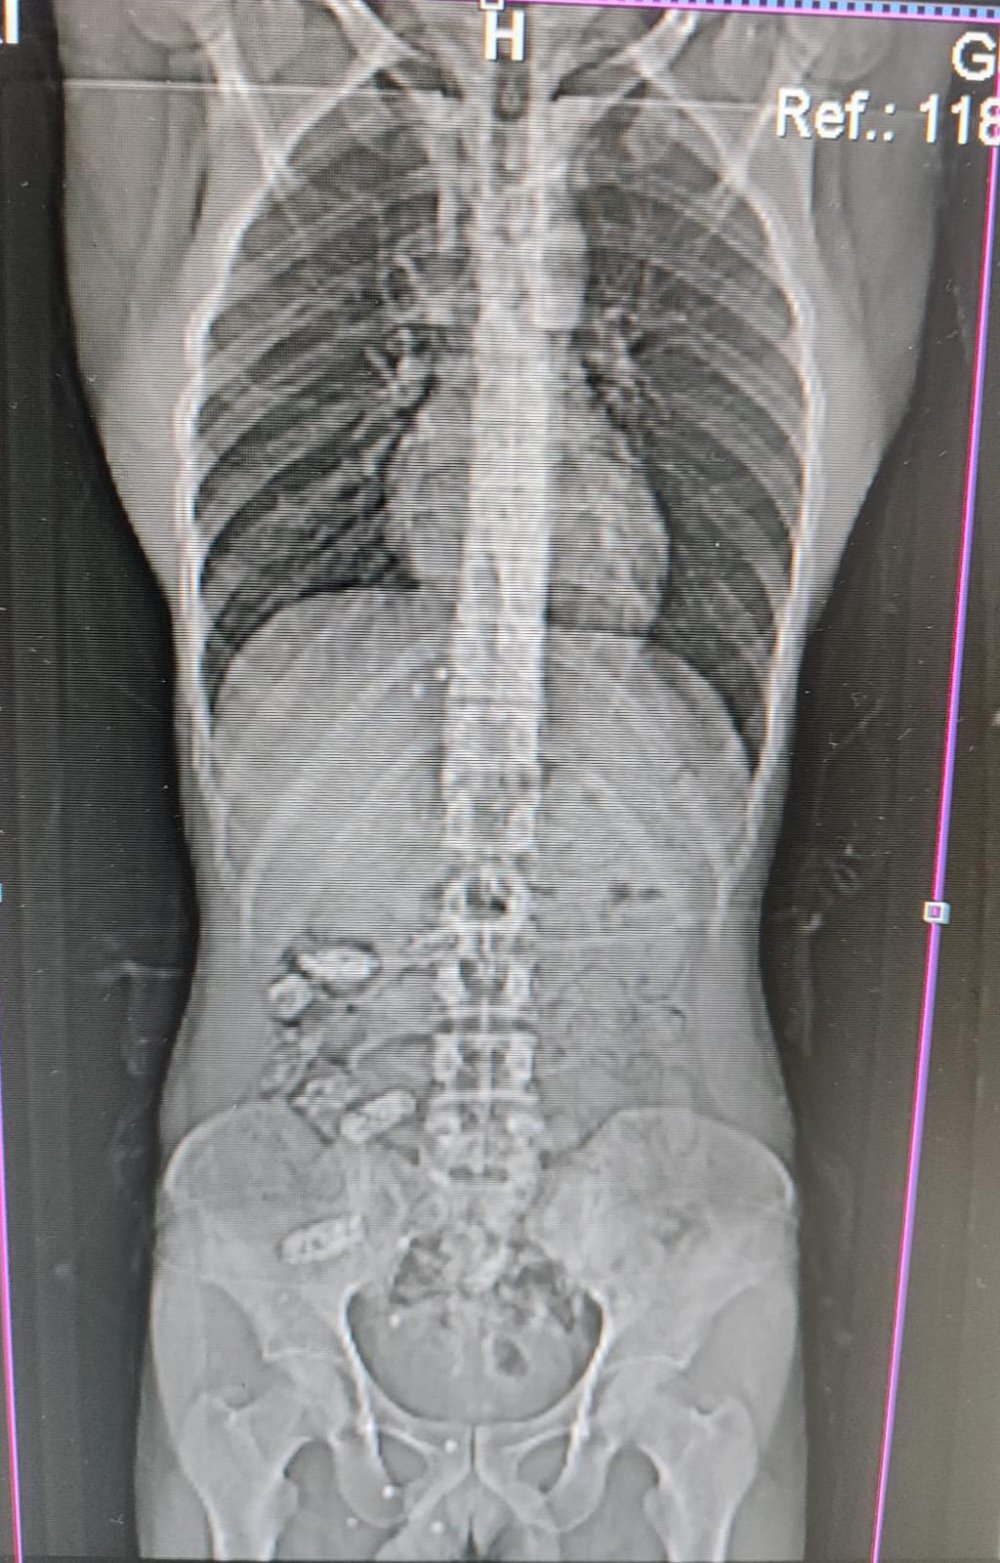

Narkotik Suçlarla Mücadele Şube Müdürlüğü ekipleri tarafından Akçakale Uygulama noktasında durdurulan bir araçta bulunan S.A adlı yabancı uyruklu şahsın uyuşturucu madde kuryesi olabileceği ve yutma suretiyle uyuşturucu madde taşıdığından şüphelenilince şahıs Gümüşhane Devlet Hastanesine kontrole götürüldü.

Burada yapılan kontrollerinde ve çekilen röntgen filmlerinde S.A’nın midesinde uyuşturucu madde olduğu tespit edilince hastanede yapılan müdahaleler sonucunda bu maddeler çıkarıldı.

Operasyonda S.A’nın midesinde toplamda 18 adet kapsül halinde 152,29 gram metamfetamin maddesi ele geçirilirken yabancı uyruklu şahıs hakkında Uyuşturucu Madde İmal ve Ticareti suçundan adli makamlarca tutuklanarak cezaevine gönderildi.